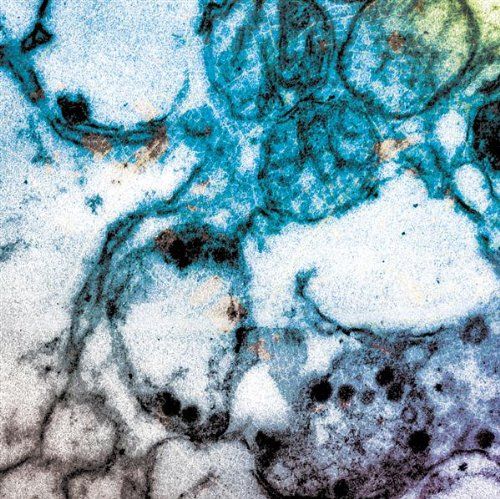

terser dino dumandan v0

500 x 499

92.86 KB